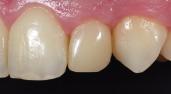

Case Study

Class IV controlled layer concept utilising G-ænial™ A’CHORD in 3 shades

This case study presents the clinical management of a patient who presented with an existing failed anterior composite, requiring a Class IV direct composite replacement. The restoration aimed to achieve seamless integration with the natural dentition while restoring form and function.

3 - Completion of the Palatal Shelf and interproximal wall with the application of G-ænial™ A’CHORD composite, shade JE. The Interproximal wall was formed with the use of a plastic mylar strip and pull through technique to help develop an anatomical contour.

5 - A chromatic body shade, G-ænial™ A’CHORD shade A2 was then applied and extended beyond the bevel to mask the transition line. Internal anatomy in the incisal third was also sculpted and formed in this increment of composite resin. White tints, Essentia White Modifier (WM) was then utilised to accentuate the mamelons and to replicate similar characteristics present in the adjacent right central incisor.

4 - The dentine layer was then completed by the application of an opaque shade of G-ænial™ A’CHORD Shade AO2. This is to provide the correct opacity and “block out” effect of the final restoration.

Figure 1 - Pre-Operative presentation, exhibiting a failed direct composite restoration on the upper left central incisor (Tooth 21).

Figure 7 – 2-week review demonstrating the complete optical and functional G-ænial™ A’CHORD restoration on the tooth 21.

Figure 2 - Tooth surface cleaned and prepared with 37% Phosphoric Acid Etch prior to application of the adhesive with G-Premio BOND.

Figure 6 - A final translucent shade of G-ænial™ A’CHORD shade JE was then placed to bring the anatomy to full contour.